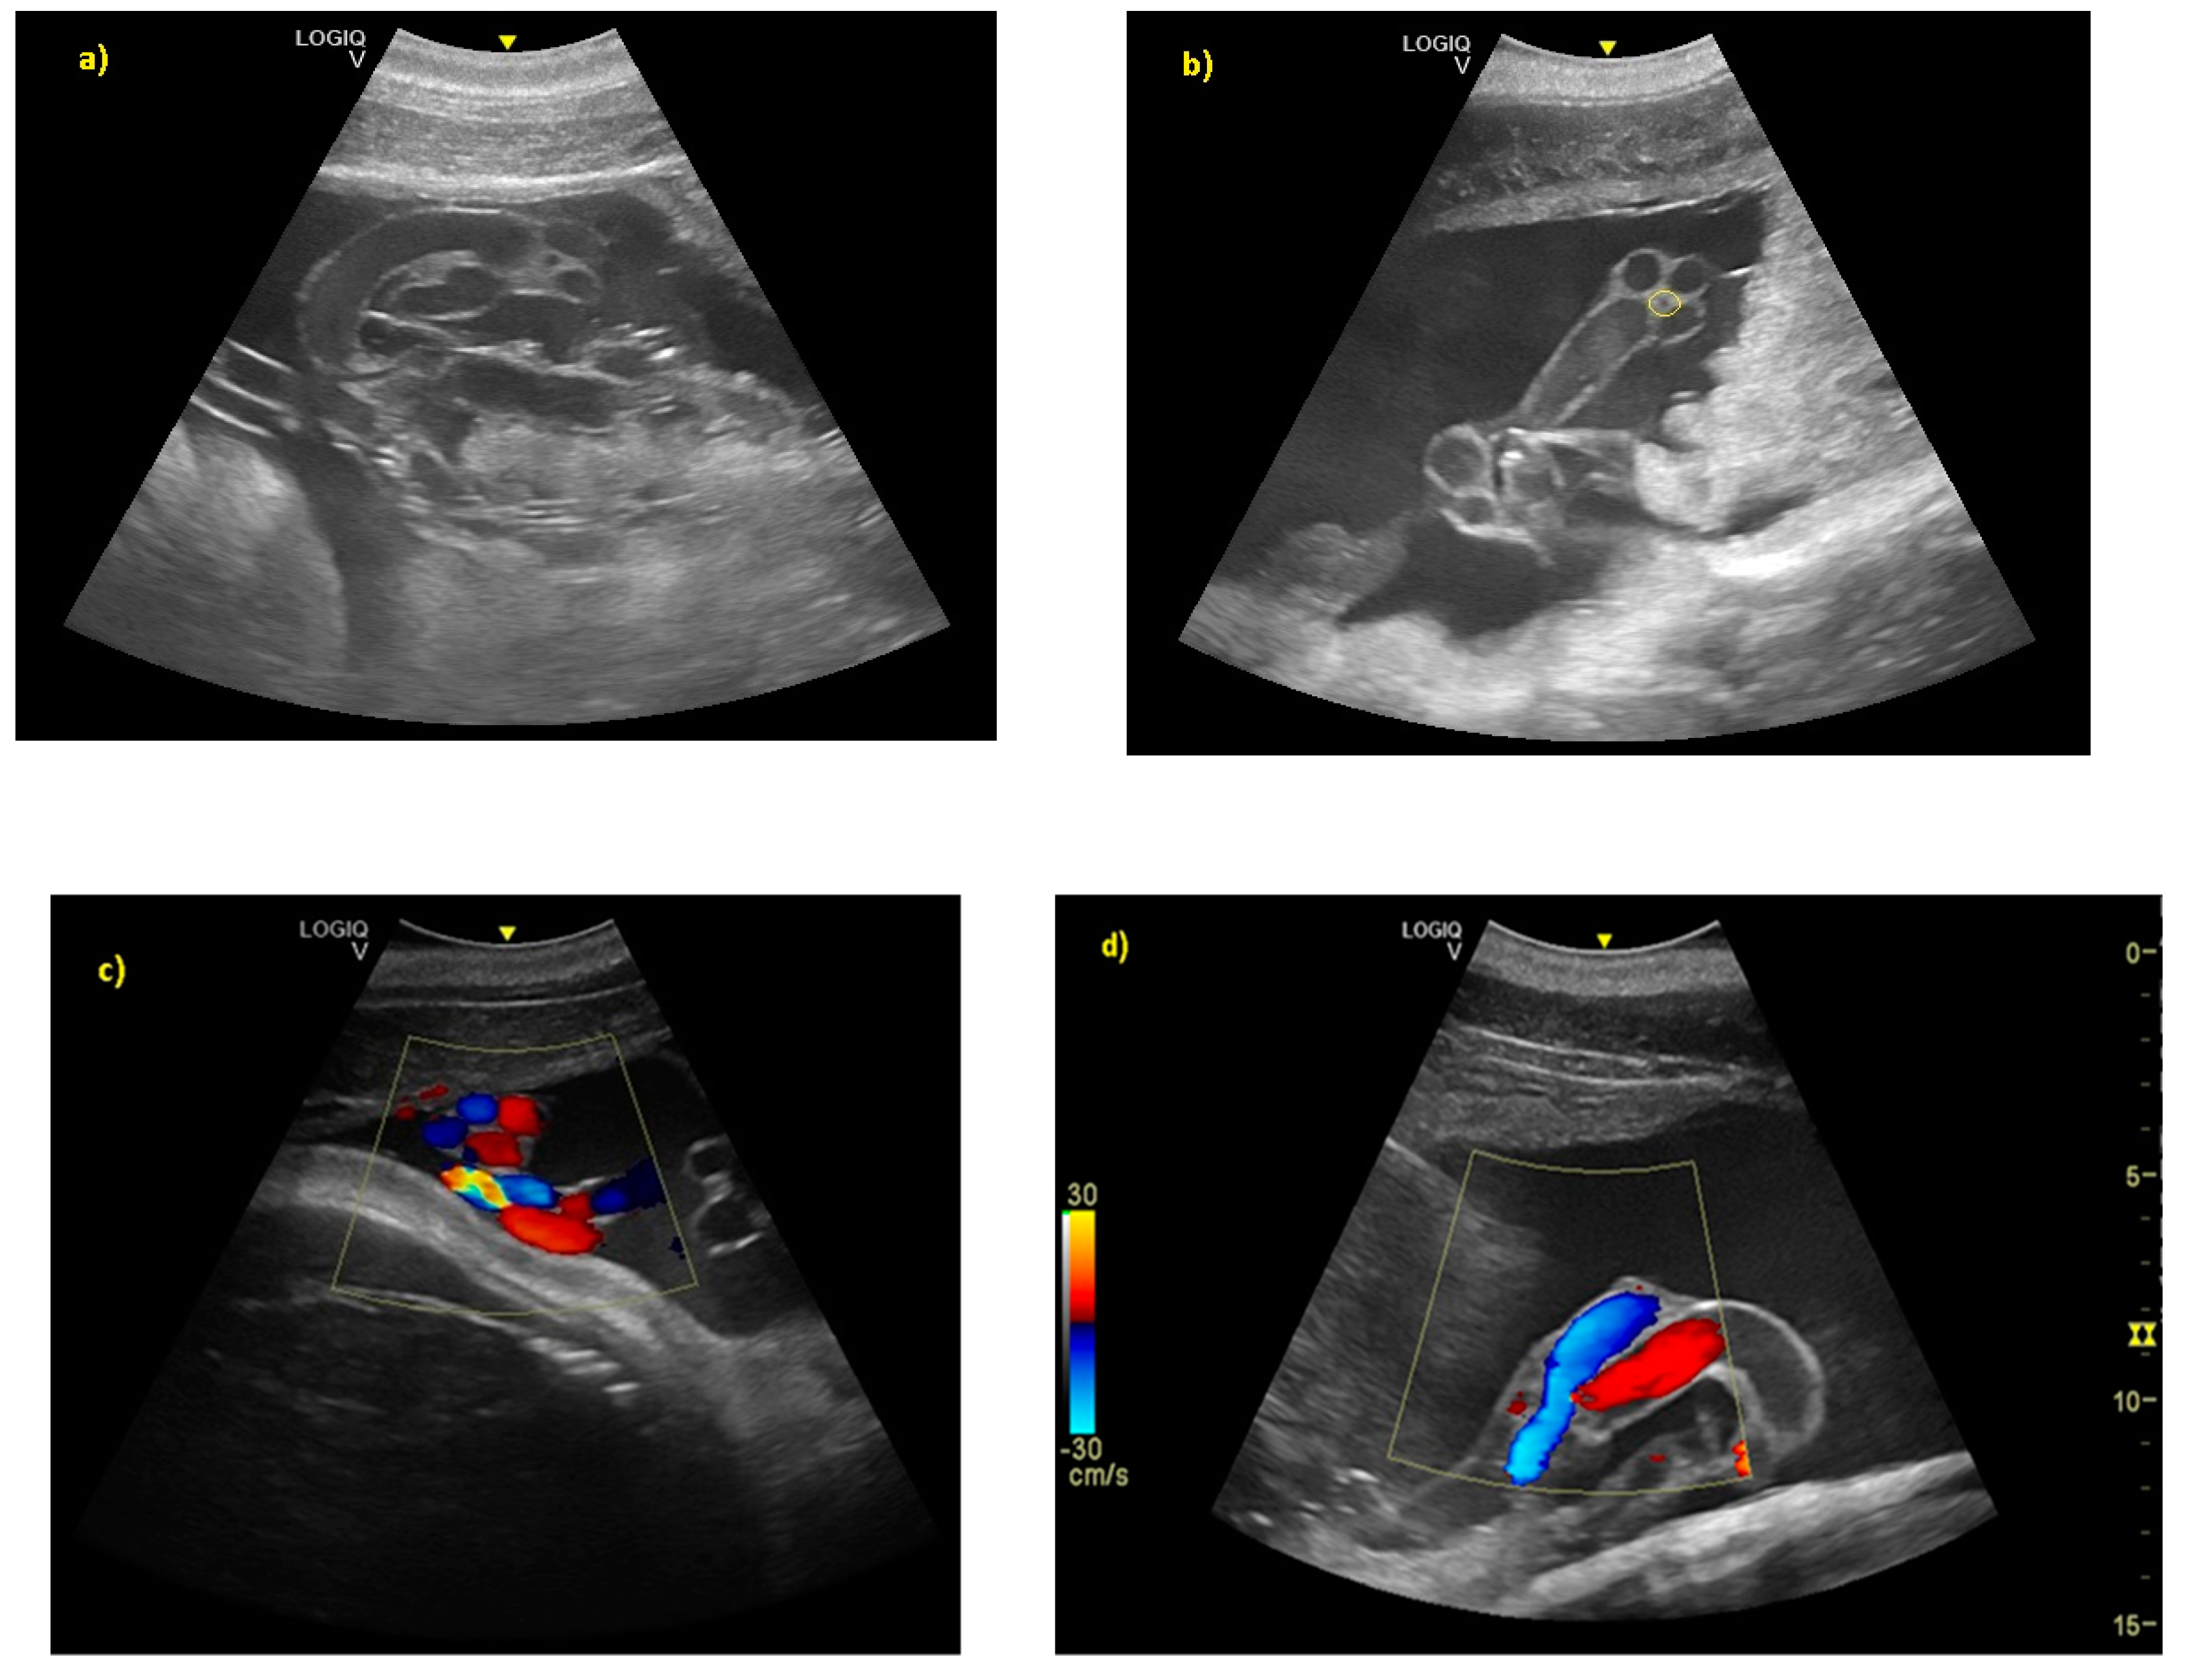

- Ivančič, M.; Gomez, F.M.; Musser, W.B.; Barratclough, A.; Meegan, J.M.; Waitt, S.M.; Llerenas, A.C.; Jensen, E.C.; Smith, C.R. Ultrasonographic findings associated with normal pregnancy and fetal well-being in the bottlenose dolphin (Tursiops truncatus). Vet. Radiol. Ultrasound 2020, 2020, 1–12. [Google Scholar]

- Sklansky, M.; Renner, M.; Clough, P.; Levine, G.; Campbell, M.; Stone, R.; Schmitt, T.; Chang, R.K.; Shannon-Rodriguez, J. Fetal Echocardiographic Evaluation of the Bottlenose Dolphin (Tursiops truncatus). J. Zoo Wildl. Med. 2010, 41, 35–43. [Google Scholar] [CrossRef] [PubMed]

- Rychik, J.; Ayres, N.; Cuneo, B.; Gotteiner, N.; Hornberger, L.; Spevak, P.; Van der Veld, M. American Society of Echocardiography guidelines and standards for performance of the fetal echocardiogram. J. Am. Soc. Echocardiogr. 2004, 17, 803–810. [Google Scholar] [CrossRef] [PubMed]